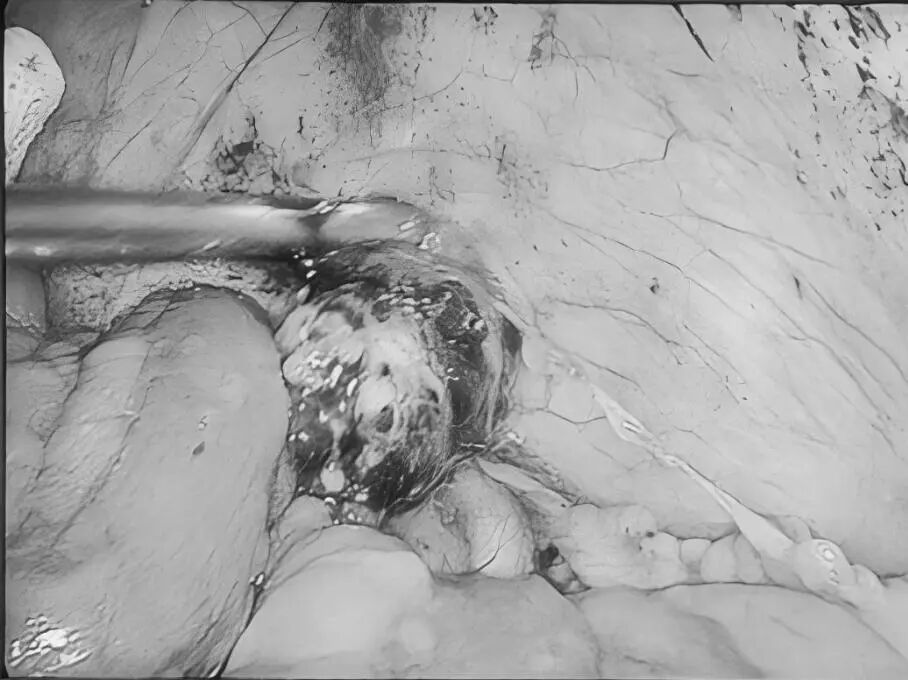

为更好地服务广大患者,贵州航天医院知名肛肠外科专家高大勇教授,每周二上午将固定坐诊贵州航天医院普外科。 坐诊信息 时 间:每周二上午(8:00-11:30) 地 点:贵州航天医院门诊部106诊室(普外科门诊) 挂号通道: 1.门诊大厅或诊室自助挂号缴费机。 2.门诊挂号缴费窗口。 3.贵州航天医院微信公众号预约挂号。 专家简介 高大勇 普外科(肛肠外科)学科带头人、名誉主任,主任医师、教授 临床擅长:对中西医结合诊治肛肠学科各种常见病、多发病及疑难杂症等具有丰富的临床经验。 原遵义市第一人民医院(遵义医科大学第三附属医院)、遵义市中医院肛肠科主任。中华中医药学会肛肠分会常委,全国中医肛肠学科名专家,中国健康促进与教育协会肛肠分会常委,中国康复医学会肛肠疾病康复专业委员会常委,中国民间中医医药研究开发协会肛肠分会副秘书长,中国医师协会中西医结合肛肠医师专业委员会常委,国家二级心理咨询师,贵州省第一批中医名医工作指导老师,遵义市名中医,遵义市肛肠学会会长,遵义市肛肠质控中心名誉主任,遵义市中西医结合学会名誉会长,遵义市健康科普专家,原贵州省中西医结合学会肛肠分会副主任委员、贵州省中医肛肠质控中心副主任、遵义市医学会医疗鉴定委员会专家、遵义市卫生系列高评委。发表论文30余篇,主编和参编医学著作5本,主持省级科研课题2项、市级科研课题2项、院级科研课题1项。 贵州航天医院 普外科简介 基本情况 贵州航天医院普外科成立于1968年,前身属于航天部O61基地3417医院外一科,1998年3417医院、3427医院合并后更名为普外科,下设胃肠外科、肛肠外科2个亚专业科室,拥有在全市较为先进的专科设备和技术,是中国疝病专科联盟单位,贵州医科大学附属医院胃肠外科专科联盟单位。开放床位40张,配备医护人员21人。 专科特色技术 普外科致力于胃肠及肛肠疾病的外科临床诊治及科研,以腹腔镜微创外科技术为本,形成以快速康复治疗胃肿瘤、结直肠肿瘤、小肠肿瘤、直肠脱垂、肥胖病、急腹症、各类疝、痔、瘘等专科特色,同时注重胃肠疾病尤其是结直肠恶性肿瘤的基础研究和临床转化研究,总体诊断和治疗水平在区域同级医院居于领先水平。 开展手术:腹腔镜下胃癌根治术,腹腔镜下袖状胃切除术,腹腔镜下胃肠道间质瘤切除术,腹腔镜下结、直肠癌根治术,胃癌、结直肠癌的精准治疗,腹腔镜下小儿疝气、成人疝修补术,腹腔镜下阑尾手术,内痔的硬化注射治疗及痔疮的微创治疗:ATH、PPH、TST,直肠脱垂的各种手术治疗,难治性伤口VSD技术,鼻胃肠管、肠梗阻导管置入术,肛肠术后间歇性导尿技术,并引进了中医适宜技术,也为各种化疗患者提供输液港安装,提高患者就医体验。 腹腔镜下腹股沟疝 无张力修补术 腹股沟疝里金斯坦(Lichtenstein)手术 PPH微创术治疗环状混合痔 黏连性或炎性肠梗阻-肠梗阻导管 腹腔镜袖状胃切除 腹腔镜阑尾切除术 腹腔镜阑尾肿瘤切除术 腹腔镜下结肠癌根治术 科室诊疗范围 胃肿瘤、结直肠肿瘤、小肠肿瘤、肥胖症、各类急腹症、腹部外伤、腹壁疝、便秘、直肠脱垂、痔疮、肛瘘、肛裂等胃肠、肛肠外科疾病。 END